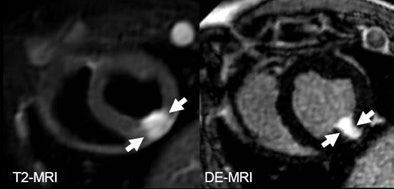

| The arrows on unenhanced CT show a hypodense area corresponding to edema as it can be seen on T2-weighetd MRI. The arrows on late-phase CT and MR correspond to infarction. The area of edema is larger than the area of infarction as expected based on previous MRI studies for the imaging of myocardial edema. All images courtesy of Dr. Andreas Mahnken. |

According to the results, mean MI sizes on unenhanced, arterial, and late-phase DSCT were 27.2 ± 8.5%, 20.1 ± 6.9%, and 23.1 ± 8.2%, respectively. The corresponding values on T2-weighted and delayed enhanced CMR were 28.5 ± 7.8% and 22.2 ± 7.7%. Size of MI on TTC staining was 22.6 ± 7.8%.

The best agreement was found in the comparison between late-phase CT (pc = 0.9356) and delayed enhanced CMR (pc = 0.9248) with TTC staining. The group also found substantial agreement between unenhanced DSCT and the T2-weighted CMR images (pc = 0.8629).

The study shows that "unenhanced DSCT provides different information about acute ischemic injury when compared with arterial and late-phase CT," Mahnken et al wrote. "Simple theoretical consideration led to the hypothesis that hypodense areas within the [left ventricular (LV)] myocardium correspond to edema, because increased tissue water content should result in a decrease of the CT values when compared with healthy myocardium."

The hypothesis is supported by the strong correlation with areas of edema on T2-weighted CMR, which are not to be confused with strongly hypodense areas on unenhanced CT. These are thought to correspond to fatty infiltrations that occur in chronic MI.